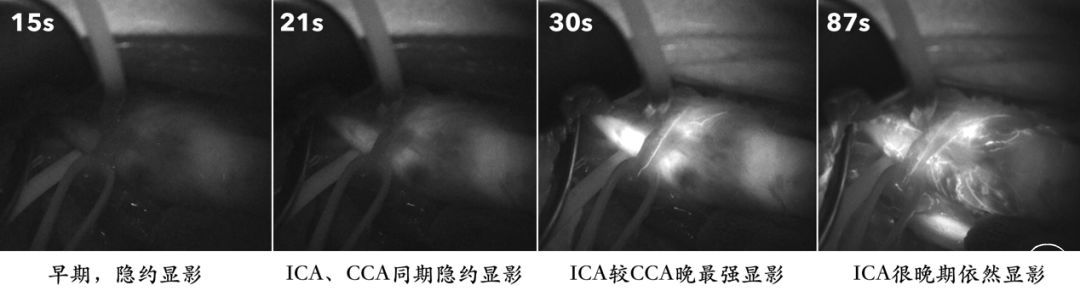

手术还是要做的,常规暴露颈动脉,ICA起始段斑块很硬,远端管腔很软还有弹性,真的不像是闭塞后的血栓形成。我们先做了一个吲哚氰绿荧光造影,发现ICA闭塞远端不但显影而且很好,只是充盈和排空都存在明显滞后。

再来看看斑块,其实很局限,从剖面来看,的确是闭塞了,而且时间不短,远端内膜已经明显增厚。闭塞远端的盲腔扩大,并有明显的新鲜血栓形成,这样的逆行血流在盲腔明显变慢并长期滞留(如吲哚氰绿荧光造影所示)从而形成血栓,并被冲刷导致脱落,这有点类似Carotid Web那样的逆向血流机理。这同时也解释了手术准备时出现的“异象”,画切口就脱落了8个栓子,消毒7个,切开皮肤还掉了5个栓子,我有那么不小心吗?![]()